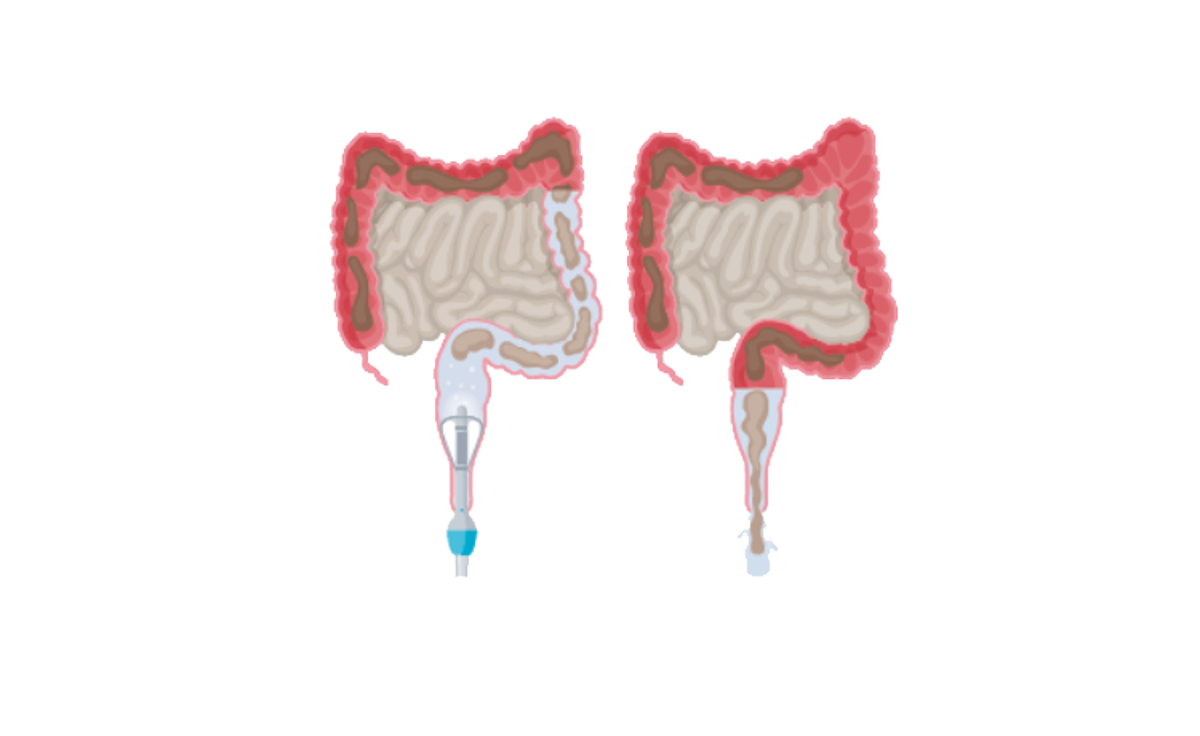

Darmspoelen of irrigeren is een kunstmatige manier om het rectum en/of deel van de dikke darm te ledigen door het inbrengen van water via het rectum, dit met behulp van een katheter of een conus. De katheter is voorzien van een opblaasbare ballon, de conus is kegelvormig. Het toegediende water veroorzaakt reflexmatige peristaltische

bewegingen die ervoor zorgen dat de ontlasting en het water worden uitgedreven zodra de katheter is verwijderd.

Hoe werkt Peristeen Plus?

- Er wordt een katheter in het rectum ingebracht.

- Via de katheter wordt water in het rectum en de dikke darm gebracht.

- De rectale katheter wordt verwijderd.

- Water en stoelgang kunnen worden afgevoerd.